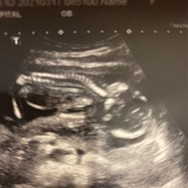

ขอดูภาพอัลตราซาวน์ หน่อยค่ะ ของเรา ทีมลูกสาวค่ะ

บ้านนี้ 18 สิงหา ค่ะ ลูกชาย 👶